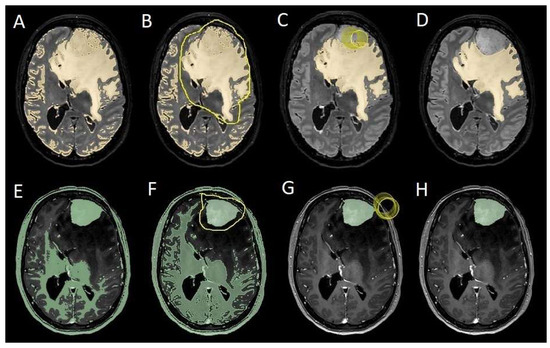

To evaluate which independent variables (meningioma volume, PE volume, the ratio between meningioma and PE volume, and the presence of preoperative epilepsy) influenced the dependent variable (seizure outcome), we performed a binomial logistic regression, which required converting continuous variables into binary values. For PE volume, values < 1 cm3 were coded as 0 (Figure 4), and values ≥ 1 cm3 as 1 (Figure 5). The cut-off was set at 3 cm3 for tumor volume, and for the volume ratio, the cut-off was 1. The absence of preoperative epilepsy was coded as 0, while its presence was coded as 1. Regarding seizure outcome, Engel IA cases were coded as 0, and cases classified as Engel > IA were coded as 1.

Figure 4. Segmentation process for PE < 1 cm3. (A,E) Automatic thresholding technique to identify initial regions of interest based on intensity values, respectively, for the PE and the meningioma. (B,F) Partially automatic erase of redundant signal with “erase outside” tool. (C) Precisely definition of boundaries of edema through manual erasure, cutting all around redundant signal. (G) Manual erasing boundaries for tumor volume. (D,H) Final segmented volumes. PE: peritumoral edema.